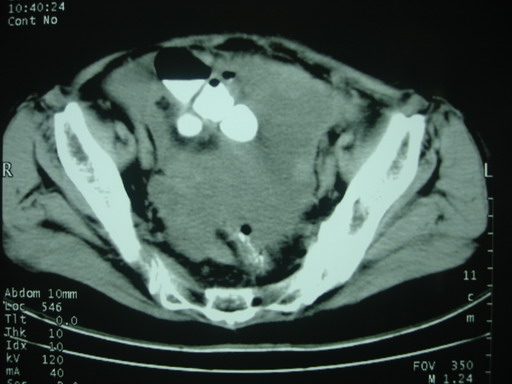

女,70岁,自述锻炼时牵拉导致左下腹疼痛,后疼痛加剧,发现包块10天,家属说其他检查,无法热,大便正常,一般情况差,痛苦面容,左下腹压痛明显,口服造影剂后腹泻,钡灌肠降结肠迂曲粘膜未见异常。抗炎治疗一周后诉症状减轻。

以下图考虑是何病?谢谢!

大网膜血肿?建议增强进一步检查。

外伤性大网膜积液、血肿?穿刺一下吧!

盆腔附件区不规则软组织密度影,与下腹部异常密度影相联,建议进一步检查除外妇科疾患!

肠系膜血肿.